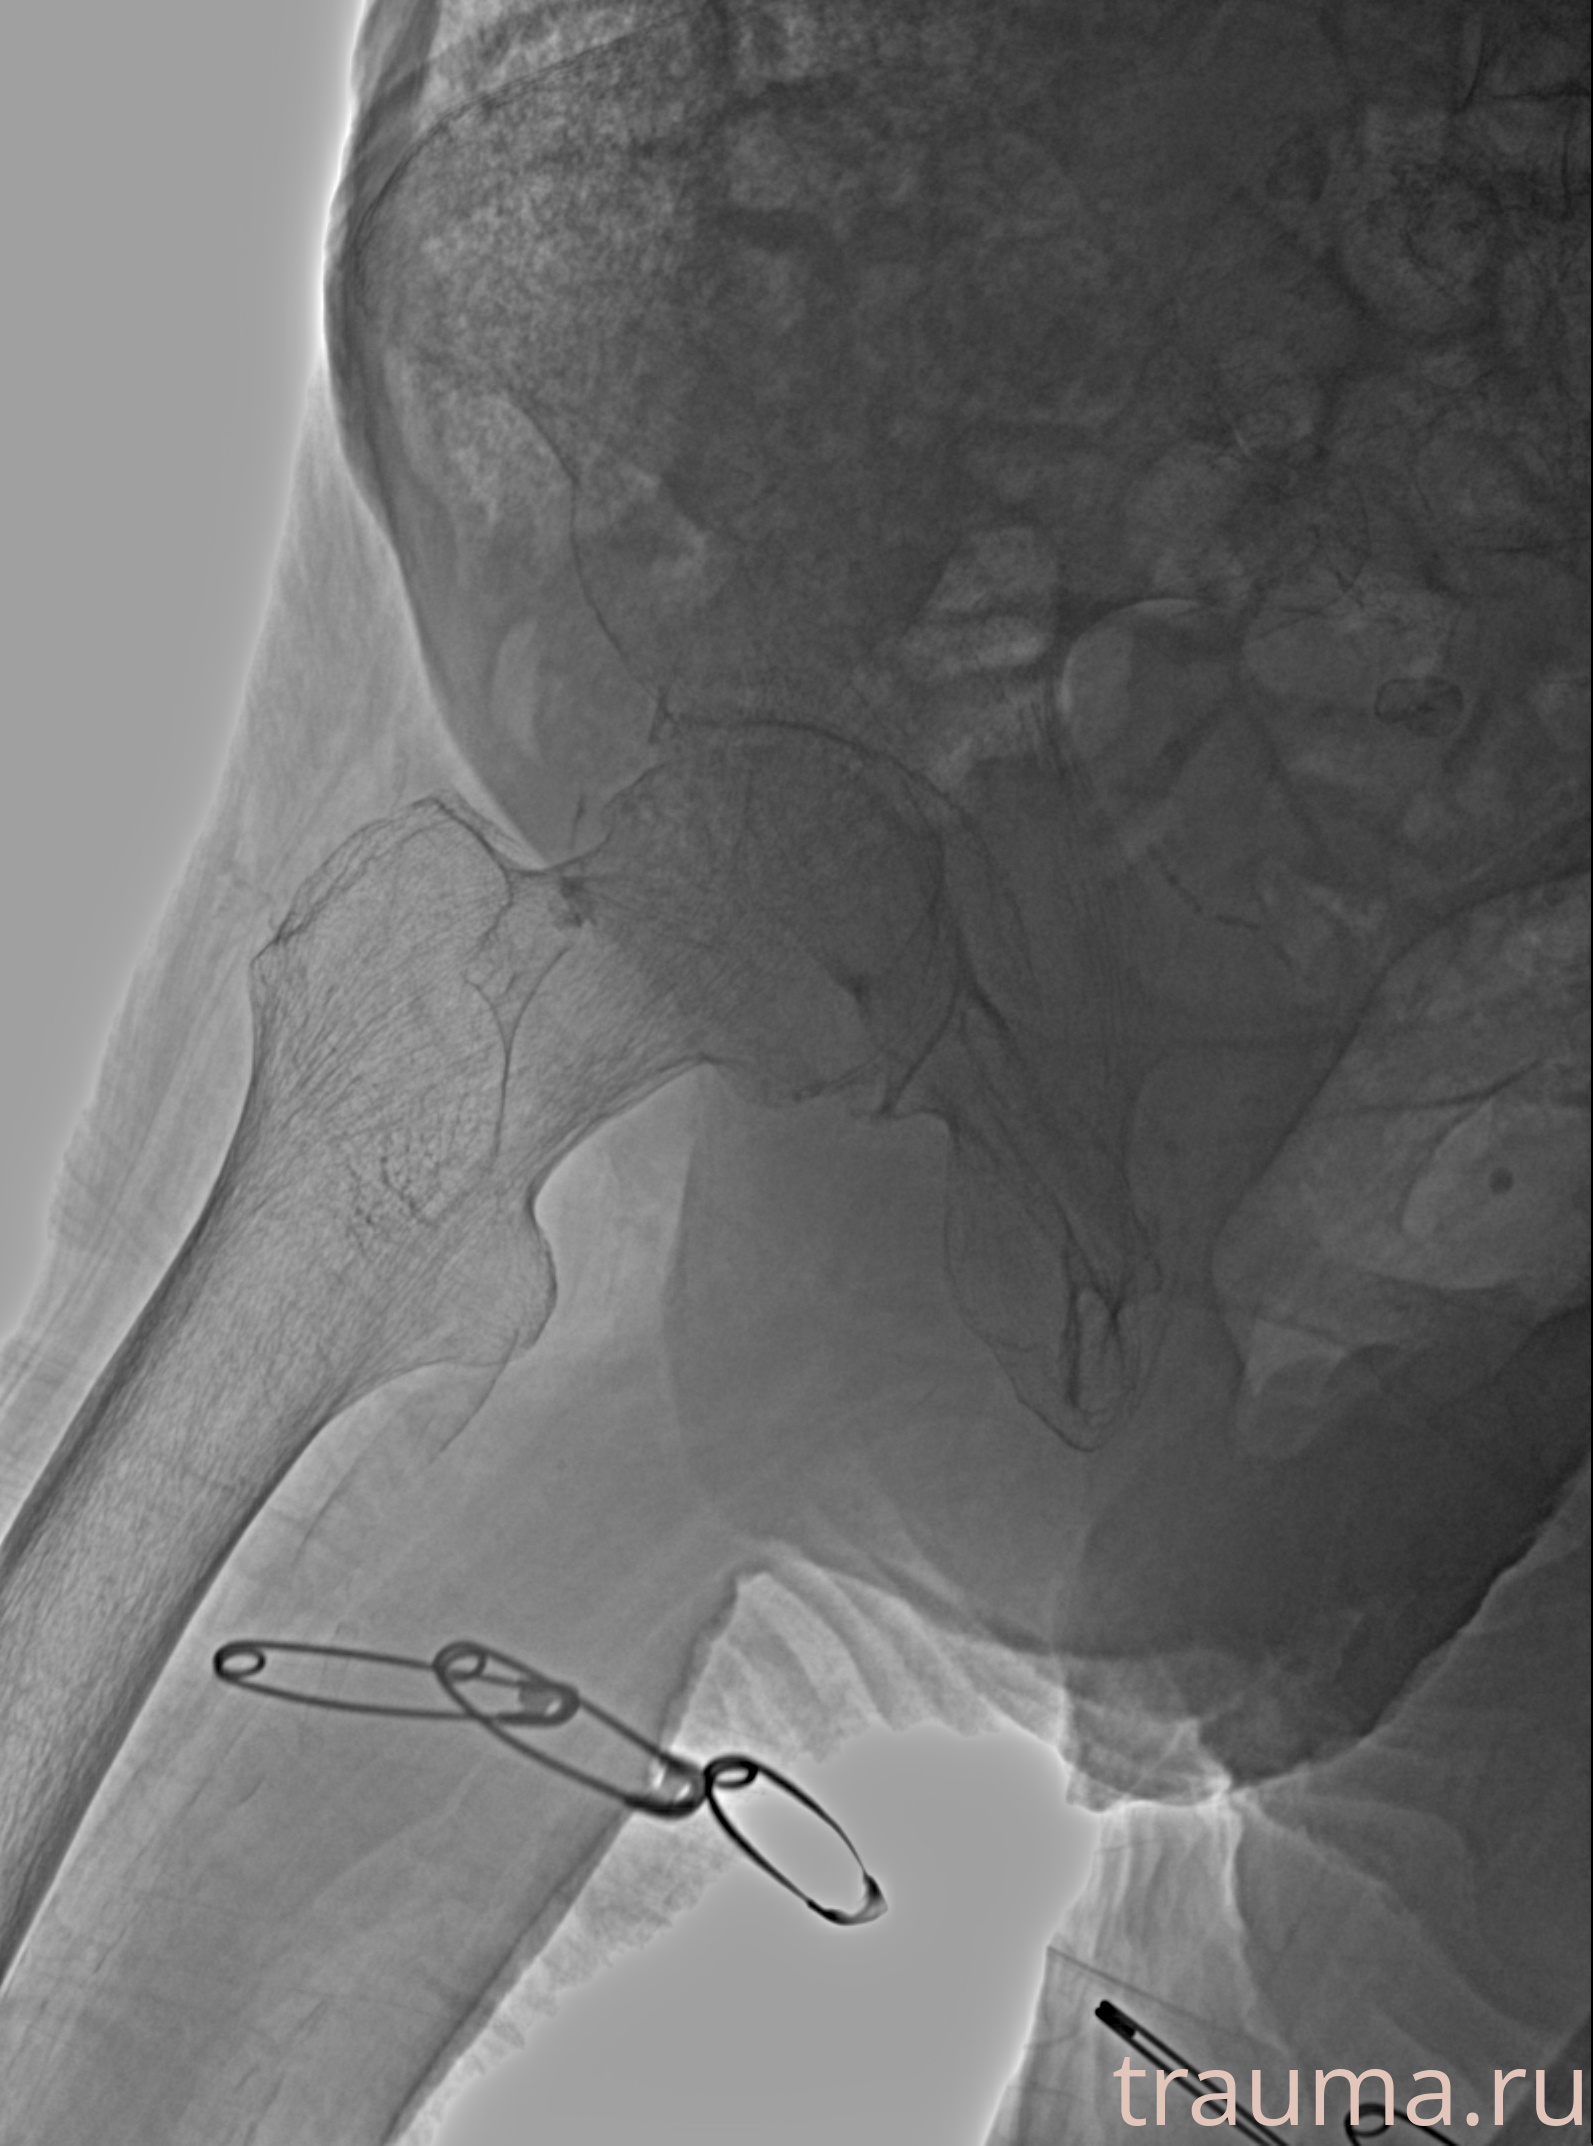

Рентген на дому: по вашему адресу приезжает врач-рентгенолог, травматолог-ортопед с мобильным рентгеновским аппаратом, проводит диагностику травмы или заболевания, делает необходимые рентгенограммы, дает рекомендации по дальнейшему лечению. Получить качественные снимки в домашних условиях возможно благодаря уникальной методике, разработанной МосРентген Центром для института  Склифосовского